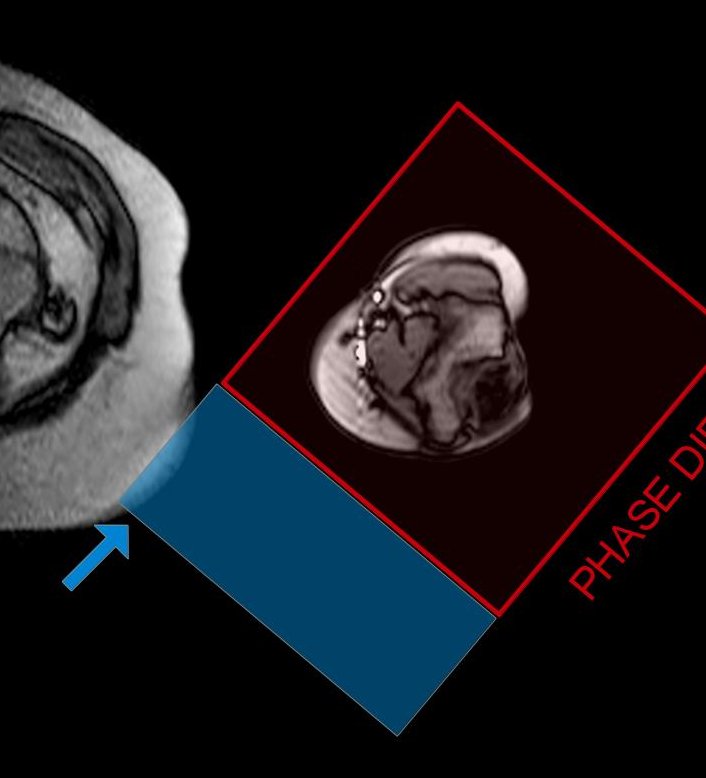

Consiglio allora di ruotare il “quadrato” in modo che i due lati paralleli del senso della fase vadano ad allinearsi lungo la direzione lungo la quale vorremo far distribuire gli artefatti.

Fig.4

Un ulteriore aspetto da valutare è che, avendo l’addome proprio sul lato della codifica di fase, potrbbe darci ribaltamento e quindi richiedere un sovracampionamento più importante.

Fig5

Ruotando il FOV molto probabilmente avremo un vantaggio significativo grazie al fatto che il ribaltamento dovrebbe essere meno esteso (solo la paerte indicata dalla freccia andrà a ribaltare). (in teoria secondo questo ragionamento potrebbe essere quasi conveniente far posizionare il braccio in posizione intraruotata con la mano in laterolaterale, ma a quel punto diventerebbe difficile mantenere un asse corretto dell’allineamento omero-radio/ulna)